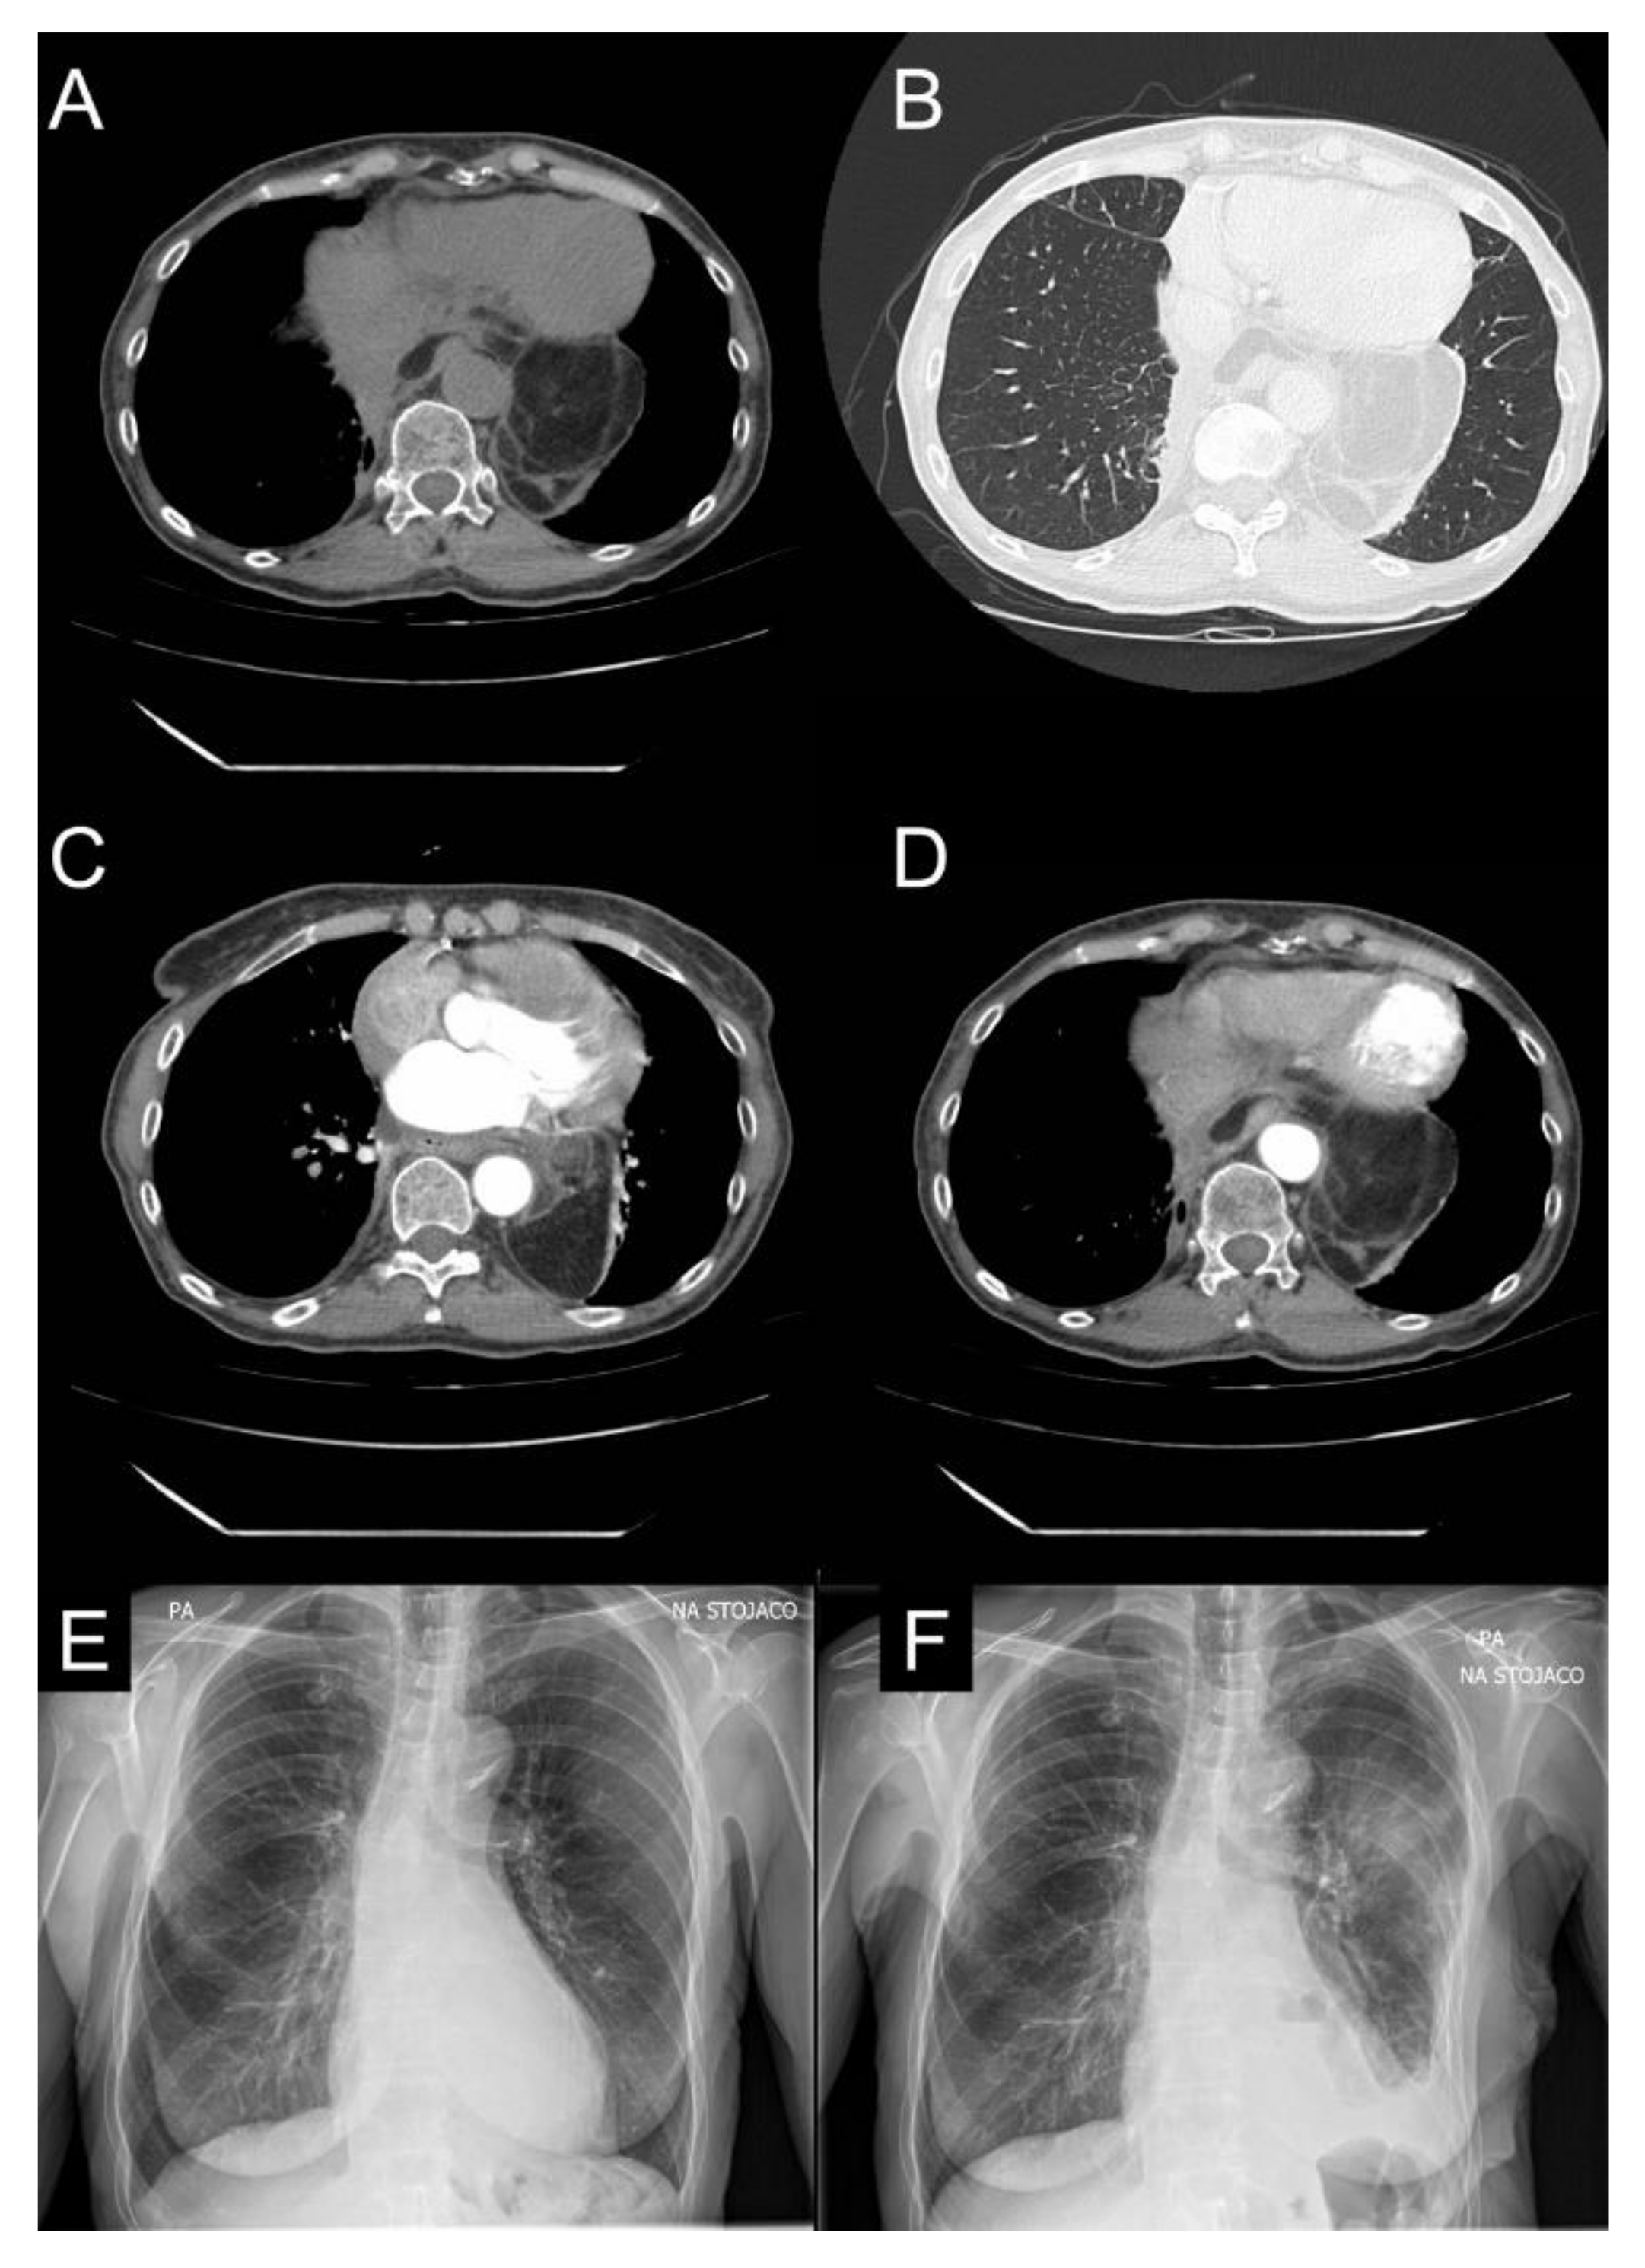

2. Case Report

5.2. Radiological Imaging